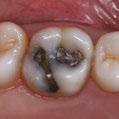

Acude a la consulta un paciente masculino de 35 años exigiendo cambios en la estética de sus dientes. El examen intraoral clínico y fotográfico reveló pérdida de estructura dentaria con facetas de desgaste en dientes anterosuperiores e inferiores, acentuándose hacia zonas oclusales de dientes posteriores.

El diagnóstico evidenció que el paciente presentaba alteración en la dinámica de la guía anterior por el desgaste de los bordes incisales, con pérdida de dimensión vertical oclusal (VDO), alteración del plano de oclusión y relaciones interoclusales inestables (Figuras 1 y 2)

Figura 1. Caso inicial. Figura 2. Vista oclusal superior.